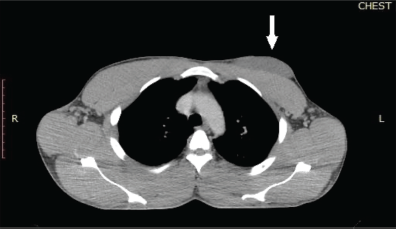

Figure 3. Reassessment chest CT scan of the patient. The lung window of a chest CT scan of the patient was done after 3 months of systemic therapy. It shows bilateral lung fields with no evidence of atelectasis or pulmonary nodules.

A repeat chest CT scan done after 3 months of treatment in May 2021 showed a 74% partial response to treatment. There was a residual left breast mass of 8.4 × 8.0 × 5.2 cm down from the pretreatment size of 13.6 × 12.0 × 8.3 cm as seen in Figure 2. All the pulmonary lesions as well as the mediastinal and axillary lymphadenopathies had resolved Figure 3. The patient continued Imatinib on account of the complete radiological response of the metastatic lesions and partial response of the primary tumour.